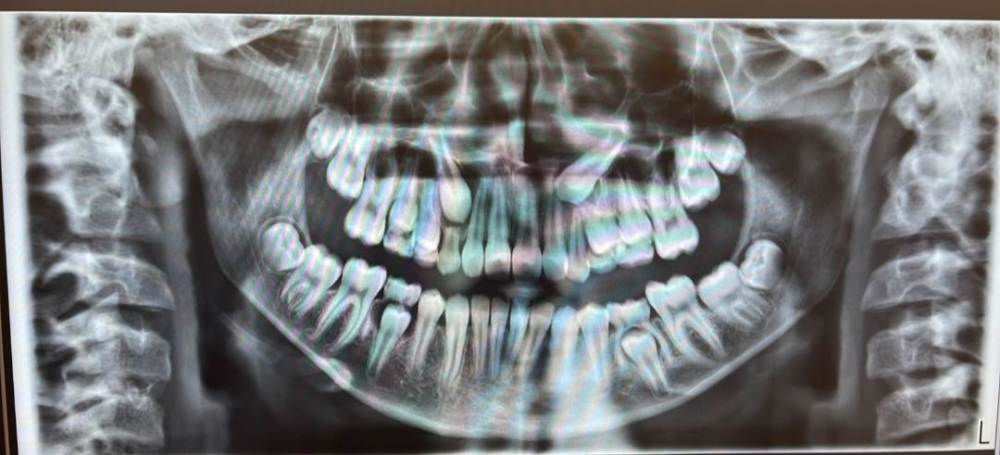

Ретинированные клыки 12 лет

Интересует ваше мнение по проведению лечения. Ребенку скоро 13 лет. Снимок сделан пол года назад. На сегодня - все молочные по снимку удалены, также удалены все восьмерки (нижние и верхние). 7-ки верхние только показались одним углом в десне, не прорезались. Места верхним клыкам понятно не хватает, еще и стоят под углом. И один из клыков стоит как-то между корнями 4-го зуба, видно на снимке.  Врач говорит брекеты нельзя, нужно элайнерами исправлять, так как тяга меньше и контролироль лучше. Сам зуб один не выйдет точно. Потом видимо будет нужно все равно его вытягивать, но это дальше будет видно. Читаю,  многие пишут про ретинированные зубы - это противопоказание для элайнеров...задумалась. Есть еще способы может и если брекеты, то можно без семерок верхних их ставить или ждать пока прорежутся все зубы, в частности 7-ки?

Здравствуйте! Видимо, Ваш врач просто любит работать на элайнерах. Не вижу причин НЕ работать в данном клиническом случае на брекетах. При работе с элайнерами возрастает риск "самовольности" пациента. Будет ли носить и не забывать, тем более в таком возрасте?

Моё личное мнение: только бы на самолигирующих брекетах вела бы такого пациента. Ждать прорезывания 7 не обязательно